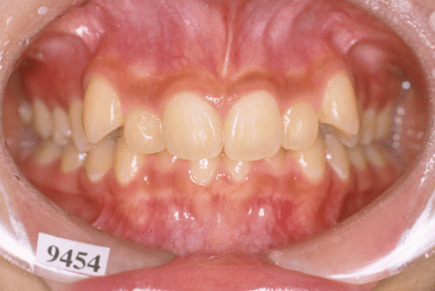

通常の場合(バランスが良い状態)